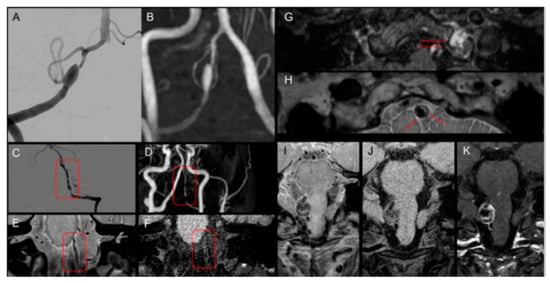

| Angiographic finding | ||

| Fusiform dilatation | 12 (44.4%) | 11 (40.7%) |

| Pearl–string sign | 16 (59.2%) | 16 (59.2%) |

| Dissection sign | ||

| Double-lumen sign or intimal flap | 21 (77.7%) | 6 (22.2%) |

| Intramural hematoma | 20 (74.0%) | Not evaluated |